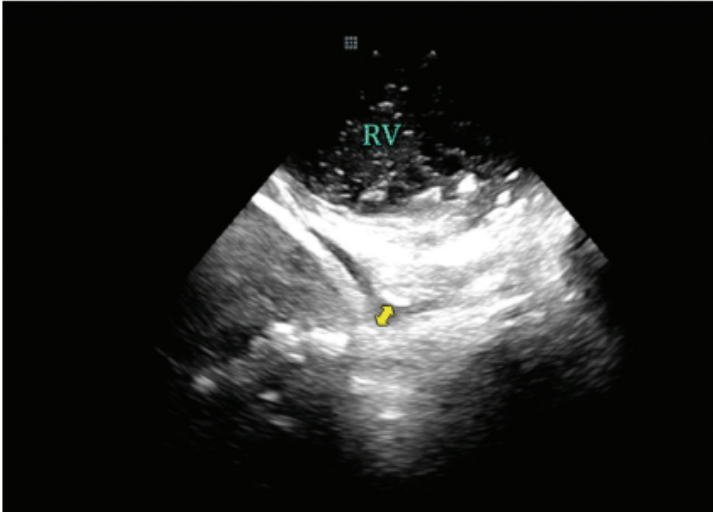

Once in the RA, the ICE catheter was minimally rotated clockwise or counterclockwise until the “home view” was seen. The home view is where the RA, tricuspid valve (TV), right ventricle (RV), and aortic valve (AV) are seen (Figure 1). From this position, an anterior curve was applied to the ICE catheter prior to advancing the ICE catheter across the tricuspid valve and into the RV. Once in the RV, the anterior curve was released and the catheter was used to assess for the presence of any pericardial effusion around the RV (Figure 2). To assess for fluid around the LV, the ICE catheter was rotated clockwise until the LV was in view (Figure 3). These images were stored and served as a useful comparator in the event of hypotension later in the case.